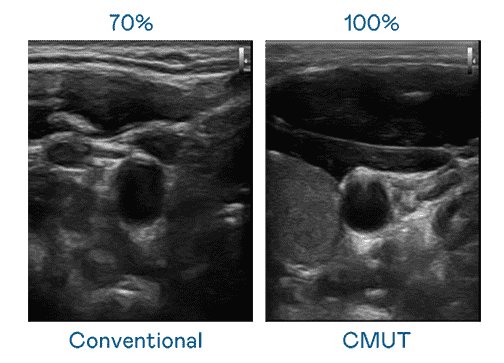

CMUT 技术是一种用电容式微机电元件来产生超音波讯号的技术。。。与传统 PZT 压电式技术相比,,CMUT 频宽增加 30%,,,,更宽频的超音波讯号让影像解析度大幅提升,,,是实现高影像品质医疗超音波扫描、、促进精准医疗发展的关键技术。。。

大频宽带来超清晰影像

超音波影像的解析度高低,,,,首先取决于探头能发出的讯号频宽。。龙门国际 CMUT 可提供高清晰的超音波讯号,,,,提供高频宽、、、高灵敏度、、、、影像纹理细节更高的超音波影像,,协助医护人员缩短影像判读时间及利用精准的医疗影像进行诊断。。